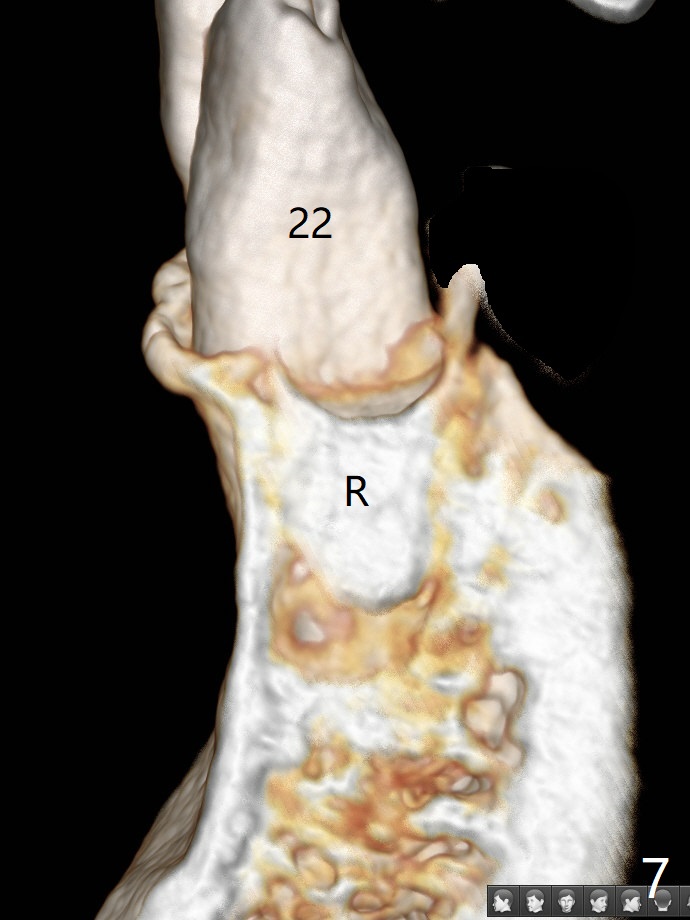

A 52-year-old man chooses to take care of the teeth #21 and 29 first due to finance (Fig.1). The implant diameter should not be too large because of the moderate mesiodistal space (Fig.2,3). Since the buccal plate of #21 is indistinct (socket shield will be done), the implant should be a little more lingually placed than the design in Fig.3, although the implant placement level seems to be acceptable. Socket shield seems to be necessary.